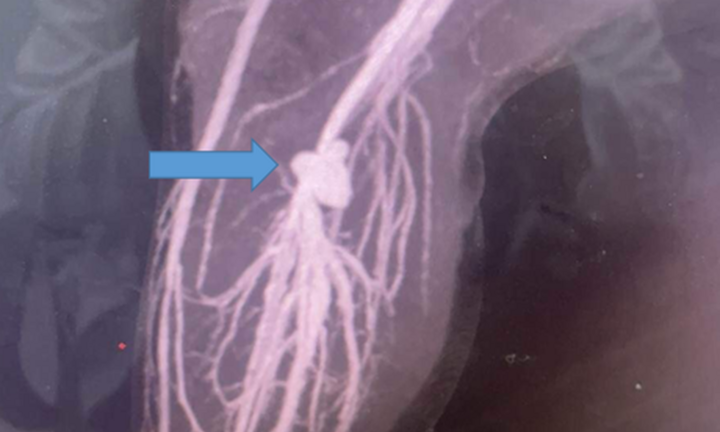

Kết quả chụp cắt lớp sọ não cho thấy có dị vật kim loại nằm ngay cạnh mắt phải, găm vào xương sọ. Bệnh nhi nhanh chóng được gây mê, phẫu thuật mở vết thương kiểm tra và lấy được dị vật là viên đạn chì, kích thước 5mm. Hiện, sức khỏe của bệnh nhi đã phục hồi, dự kiến sẽ sớm xuất viện.